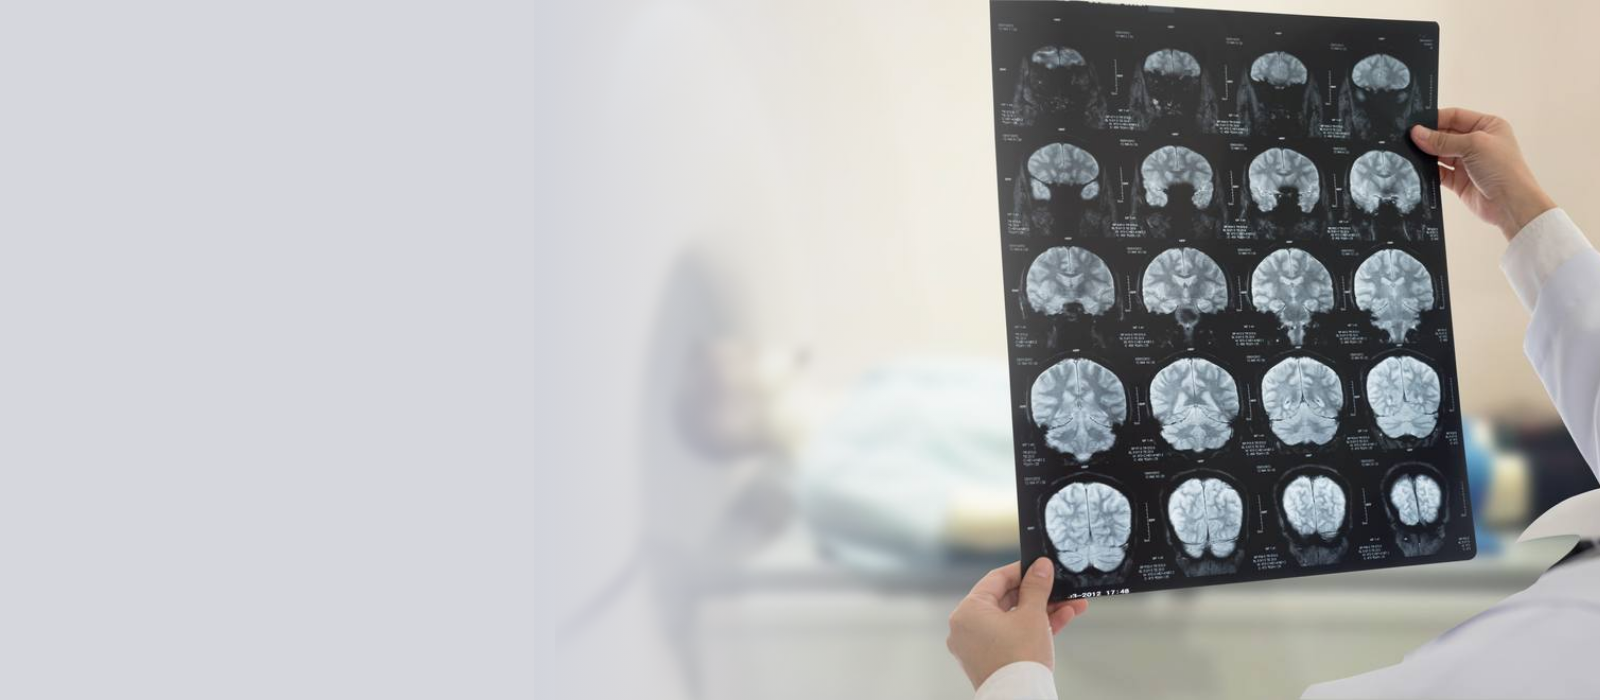

Brain tumor surgery can be performed using open surgery or minimally invasive endoscopic approaches. Open surgery involves craniotomy, where part of the skull is removed to access the tumor. Endoscopic approaches use small incisions and a camera to remove or biopsy the tumor, resulting in quicker recovery times. The choice depends on the tumor's size, location, and type.

Minimally invasive brain surgery involves the use of small incisions and advanced instruments, like endoscopes, to perform procedures with less damage to surrounding tissues. It's used for certain brain tumors, hydrocephalus, and other conditions located in difficult-to-reach areas. Benefits include reduced scarring, faster recovery, and less postoperative pain compared to traditional surgery.